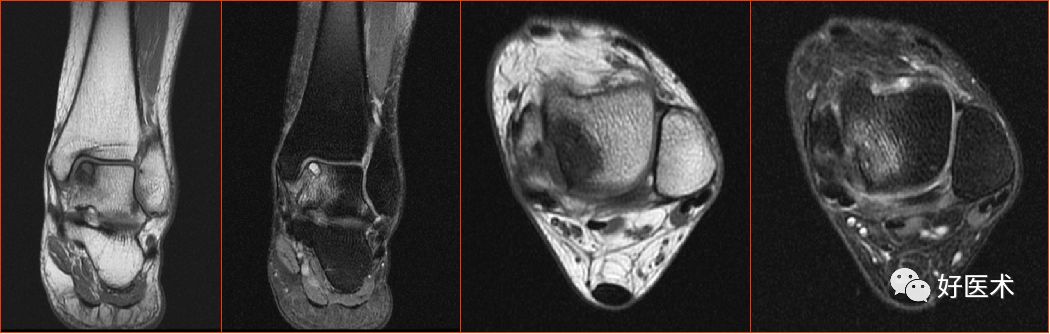

外侧副韧带

距腓前韧带

距腓前韧带撕裂

距腓后韧带

距腓后韧带部分撕裂

跟腓韧带

跟腓韧带急性完全撕裂